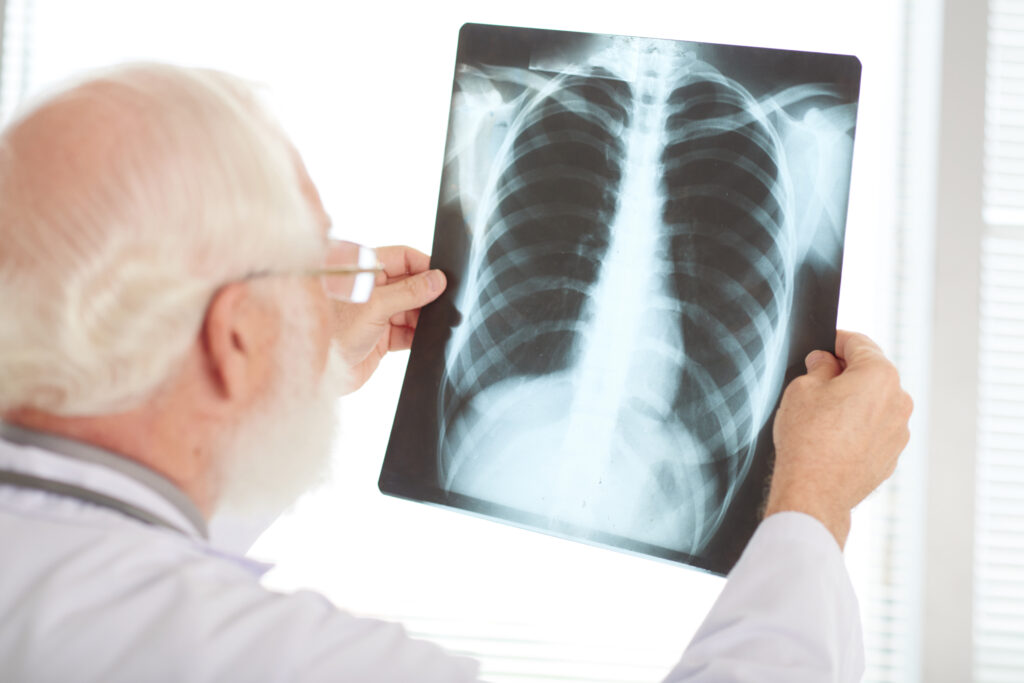

A pneumonia, que inflama os pulmões, pode ser causada por vírus, bactérias ou fungos — e costuma se instalar quando estes agentes viajam por gotículas respiratórias ou são inalados no ar. Entre os sinais de alerta estão tosse seca ou com catarro, febre alta, dor no peito, falta de ar, cansaço ou perda de apetite — embora em idosos o quadro possa surgir de modo menos evidente, com fraqueza ou confusão mental.

Especialistas reforçam que o diagnóstico precoce pode fazer a diferença: se identificado rapidamente, o tratamento é eficaz e pode evitar complicações graves, inclusive hospitalização ou sepse. Médicos pneumologistas alertam que atrasos no diagnóstico entre pessoas com doenças crônicas aumentam o risco de agravamento.